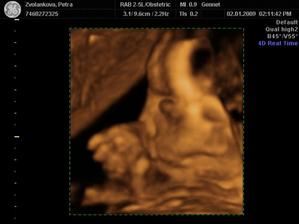

Tak jsme po UTZ,miminko se mlelo a krásně hýbalo,vše bylo vidět,vše je v pořádku a hlavně

JE TO KLUK....TAKŽE BUDEME MÍT MATYÁŠKA🙂))))))